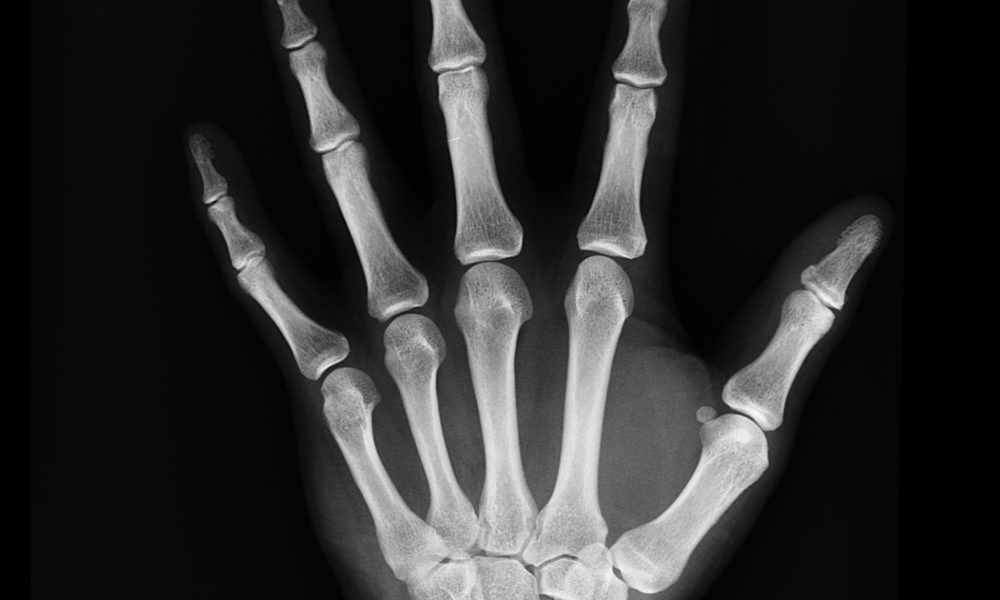

Le monde de demain : Une nouvelle technique pour déverrouiller son natel... On connaissait déjà la reconnaissance faciale ou les capteurs d’empreintes digitales pour déverrouiller...